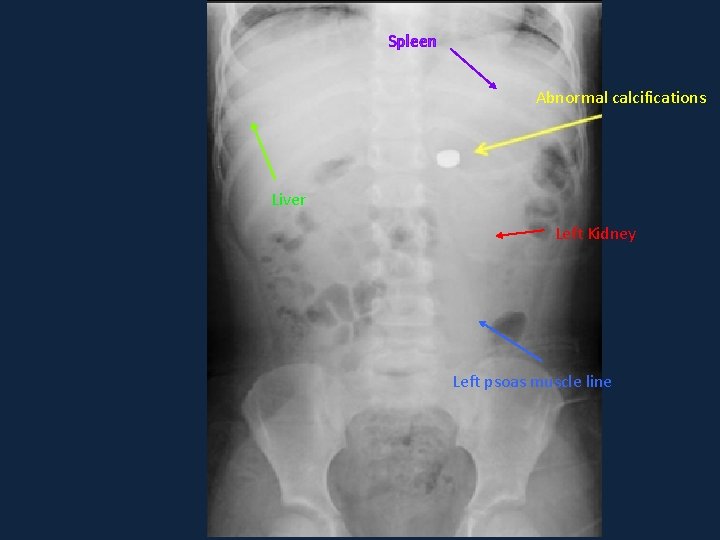

Systematic approach ►A ►B ►Calcifications and soft tissue ►Easy to miss especially soft tissue ►D because of poor contrast difference ►E ►E. g: Hepatosplenomegaly

Spleen Abnormal calcifications Liver Left Kidney Left psoas muscle line